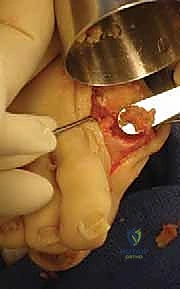

3. إعداد الأسطح العظمية

هذه هي الخطوة الأكثر أهمية. يتم إزالة كافة النتوءات العظمية (Spurs) وبقايا الغضروف التالف والمتآكل من نهاية عظمة المشط الأولى وقاعدة السلامية القريبة. يتم كشط العظم حتى الوصول إلى طبقة العظم الإسفنجي الصحي الغني بالدم (Cancellous bone)، وهو أمر حيوي لضمان التحام العظام لاحقاً.